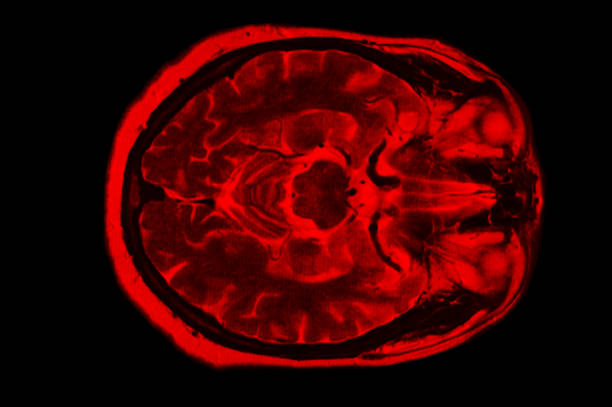

뇌경색은 뇌의 혈관이 막혀 뇌조직에 산소와 영양분이 제대로 공급되지 않아 발생하는 심각한 질환입니다. 특히 한국에서는 고령화와 함께 고혈압, 당뇨병 등 만성질환의 증가로 인해 뇌경색 환자의 수가 급격히 늘어나고 있습니다. 이는 일상생활에 큰 영향을 미치고, 적절한 초기 대응과 치료가 이루어지지 않으면 치명적인 후유증을 남길 수 있습니다. 따라서 뇌경색의 초기 증상을 정확히 파악하고, 적절한 치료 방법을 이해하며, 후유증을 최소화하기 위한 방법을 아는 것이 매우 중요합니다.

이번 글에서는 뇌경색의 초기 증상, 치료 방법, 그리고 후유증에 대해 자세히 다루어보겠습니다. 이 정보는 뇌경색에 대한 이해도를 높이고, 뇌경색의 예방과 빠른 대응에 도움이 될 것입니다.